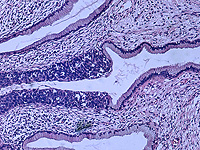

Wikipedia.org. Фото: Haymanj